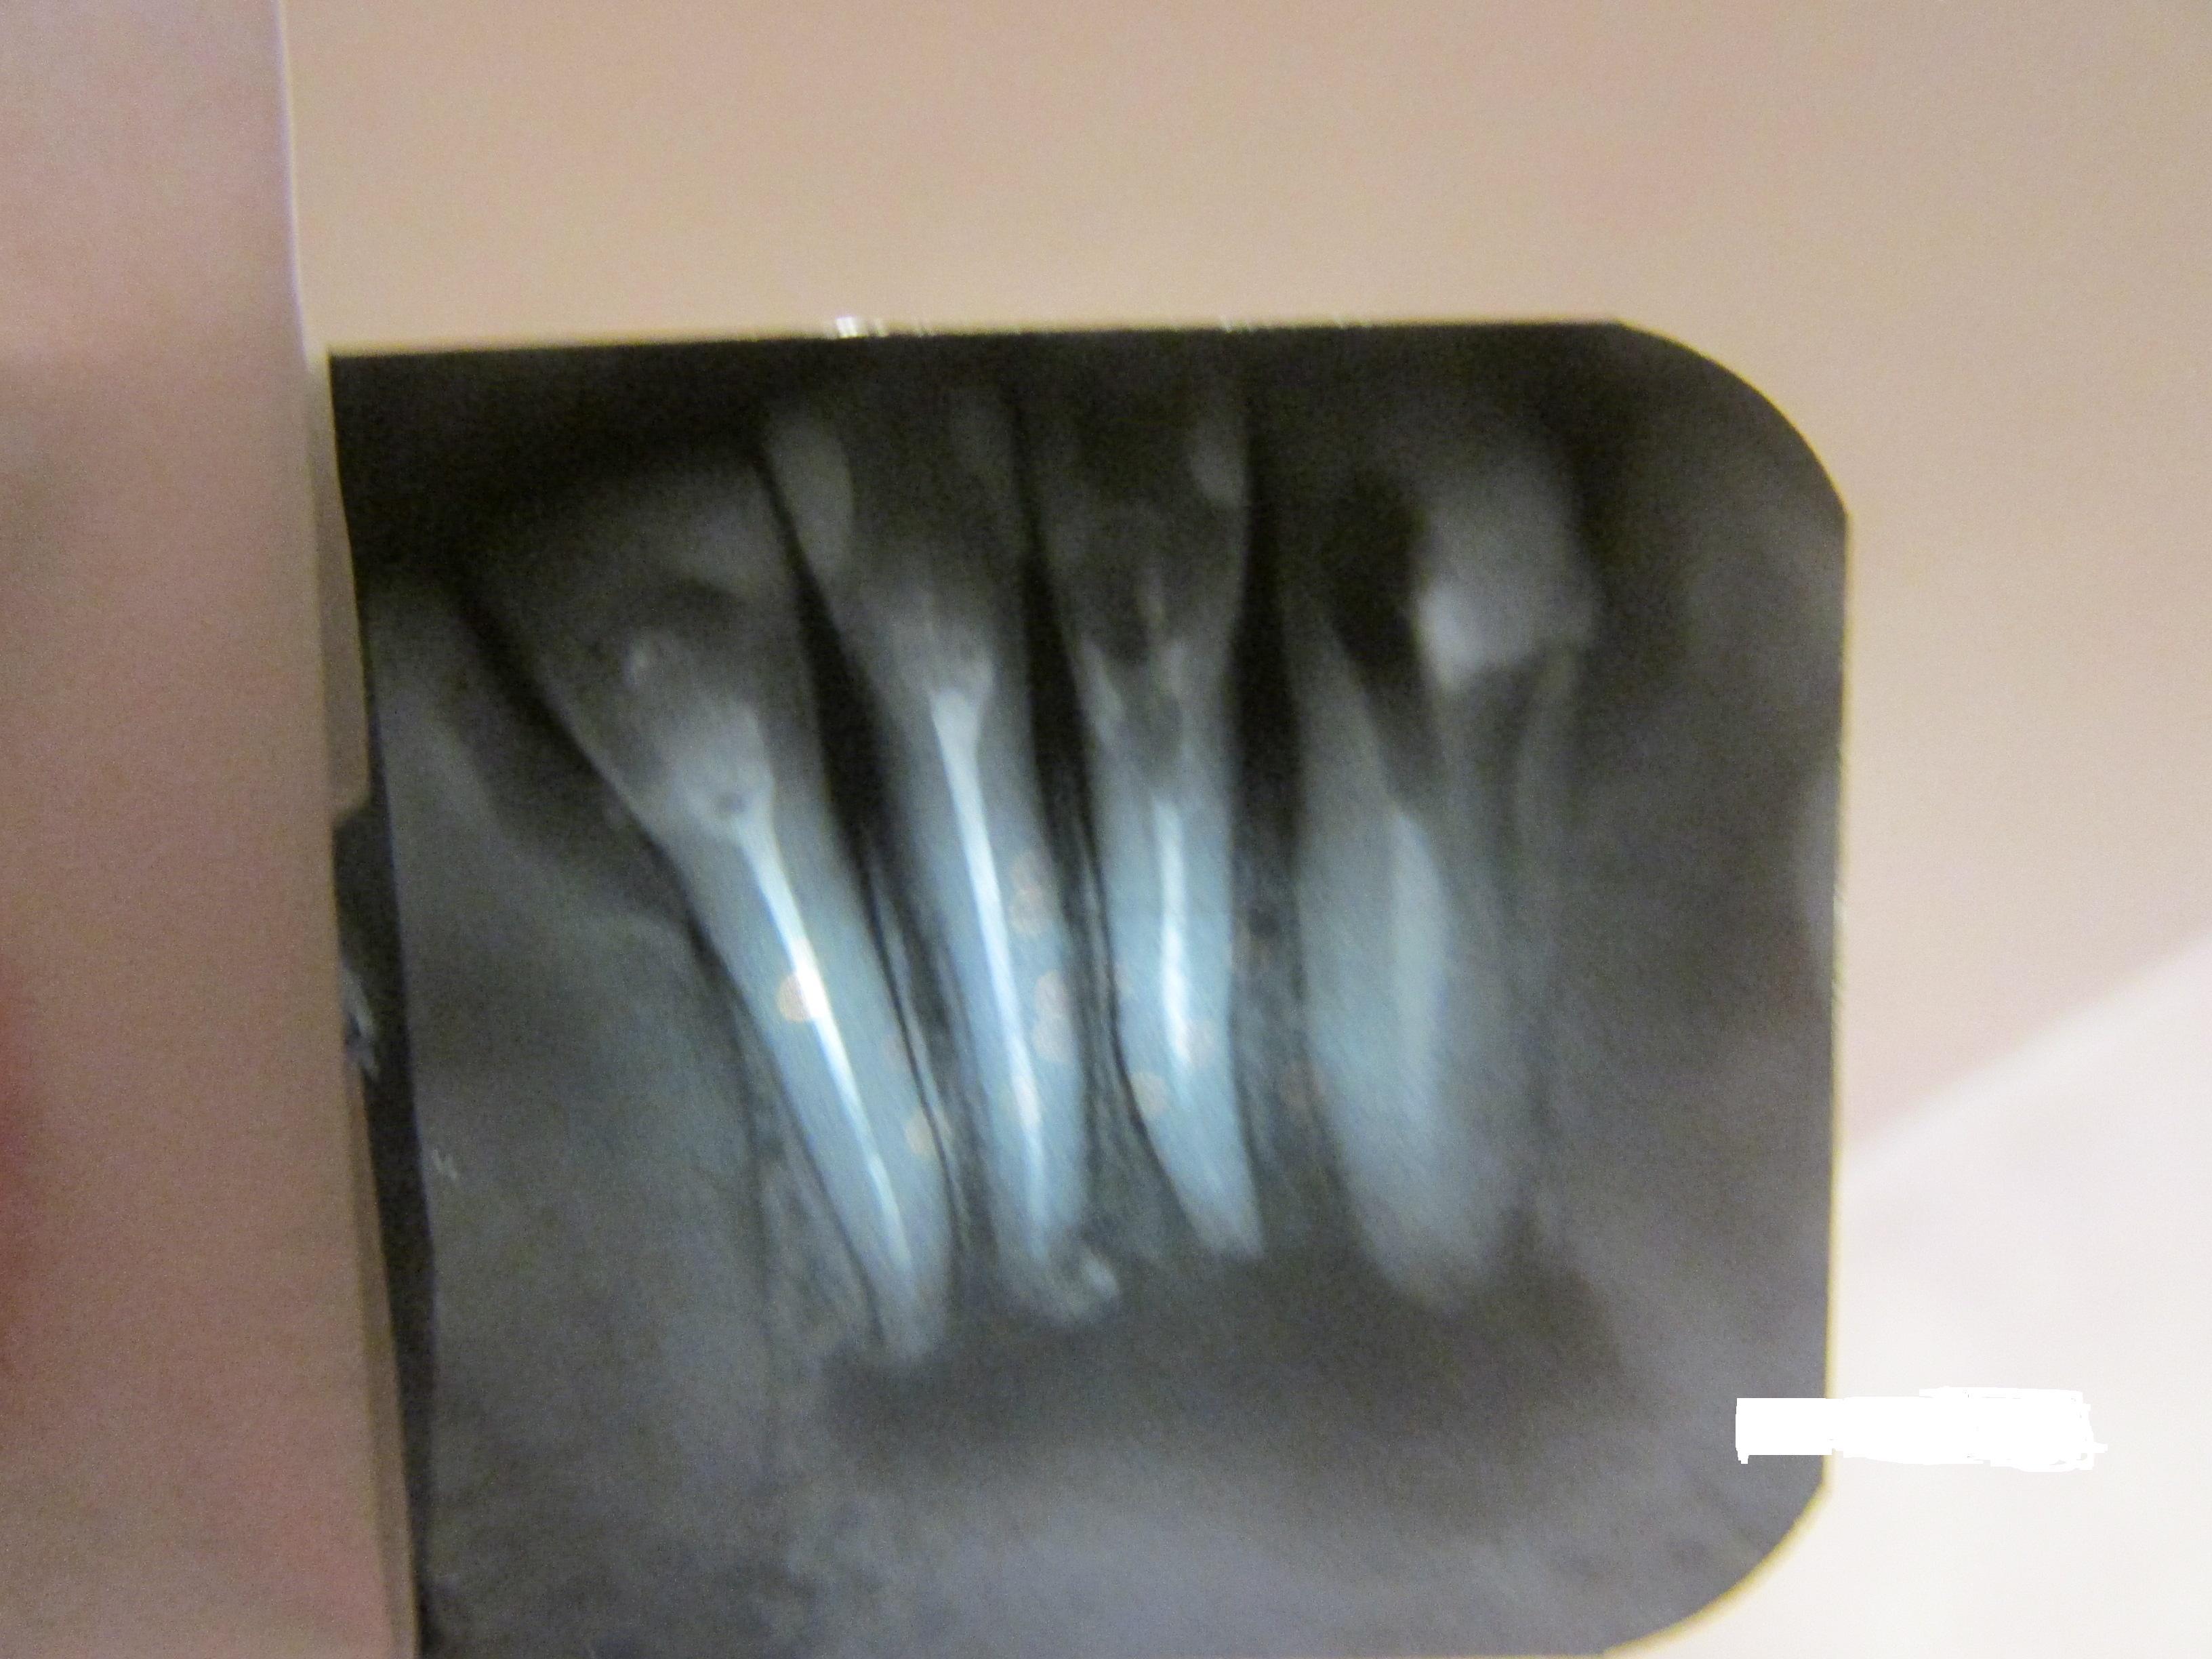

В Вашем случае эндодонтическое лечение будет вряд ли эффективно, во всяком случае это будет долго и без гарантии. Но, если Вы готовы, конечно, попробовать стоит, во всяком случае Вы ничего не потеряете.

Что касается резекции — это возможно, но резекция понадобится у корней всех этих зубов, при этом необходимо сначала снять воспаление и перед операцией хорошо запломбировать каналы.